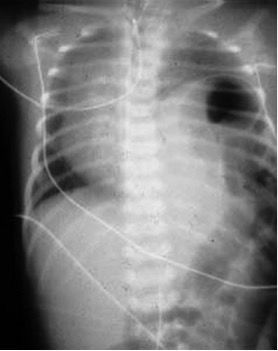

A newborn with respiratory distress within the first 24 h, with an excavated abdomen and a asymmetric chest. Auscultation with decreased breath sounds and peristaltic sounds on the affected hemithorax. The accompanying image shows the x-ray findings. What is the diagnosis?

Answer

• Congenital diapragmatic hernia.

• Intestinal obstruction

• Pneumothorax

• Pneumathocele